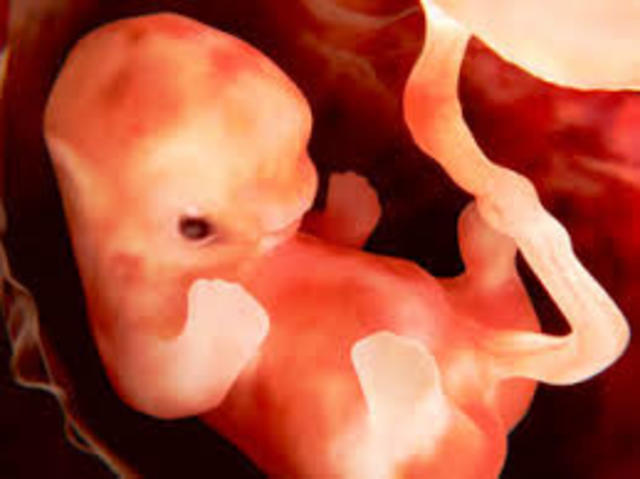

• semana 3 de embarazo

semana 3 de embarazo

Los primeros órganos empiezan a formarse. Las maravillosas células del corazón

Con solo 3 semanas de embarazo, el corazón es un grupo de células musculares aletargadas y diminutas, pero que sobre los 22 días explota de vida. Una célula se contrae espontáneamente, contagia a sus vecinas y comienza una reacción en cadena hasta que todas las células del corazón empiezan a latir.